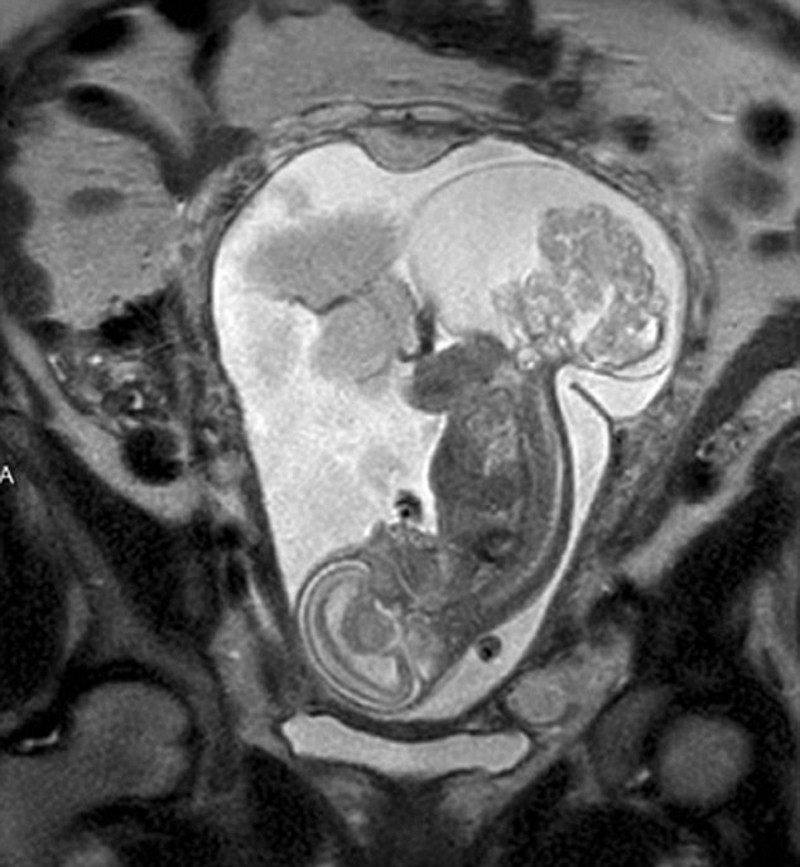

Η μητέρα της μικρής, η Μάργκαρετ, διήνυε την 16η εβδομάδα της κύησης της, όταν μετά από επίσκεψη στον γιατρό ενημερώθηκε ότι το έμβρυο είχε ένα ιεροκοκκυγικό τεράτωμα: είχε αναπτυχθεί ένας όγκος στην περιοχή του ιερού οστού και του κόκκυγά του – κάτι που παρουσιάζεται σε 1 στις 30.000-70.000 γεννήσεις.

Ο όγκος αναπτυσσόταν ραγδαία και τρεφόταν από το αίμα του εμβρύου, κάτι που σταδιακά θα προκαλούσε καρδιακή ανεπάρκεια και θα οδηγούσε στον θάνατό του. Ο μόνος τρόπος για να σωθεί, ήταν να υποβληθεί σε μια πρωτοποριακή και συνάμα επικίνδυνη χειρουργική επέμβαση, που πρότειναν οι γιατροί της εμβρυϊκής κλινικής του Νοσοκομείου Παίδων του Τέξας και η οποία απαιτούσε την εξαγωγή του εμβρύου από τη μήτρα της μητέρας του.

Μετά από 28 εβδομάδες κύησης οι γιατροί έβγαλαν το έμβρυο από τη μήτρα της μητέρας του και κατάφεραν να αφαιρέσουν τον όγκο σε μια πολύπλοκη επέμβαση, που διήρκεσε πέντε ολόκληρες ώρες.

Στη συνέχεια οι γιατροί τοποθέτησαν και πάλι το έμβρυο στη μήτρα της μητέρας του, και 12 εβδομάδες αργότερα η Λίνλι ήρθε στον κόσμο με καισαρική για να (ξανα)αντικρίσει το φως της ζωής…